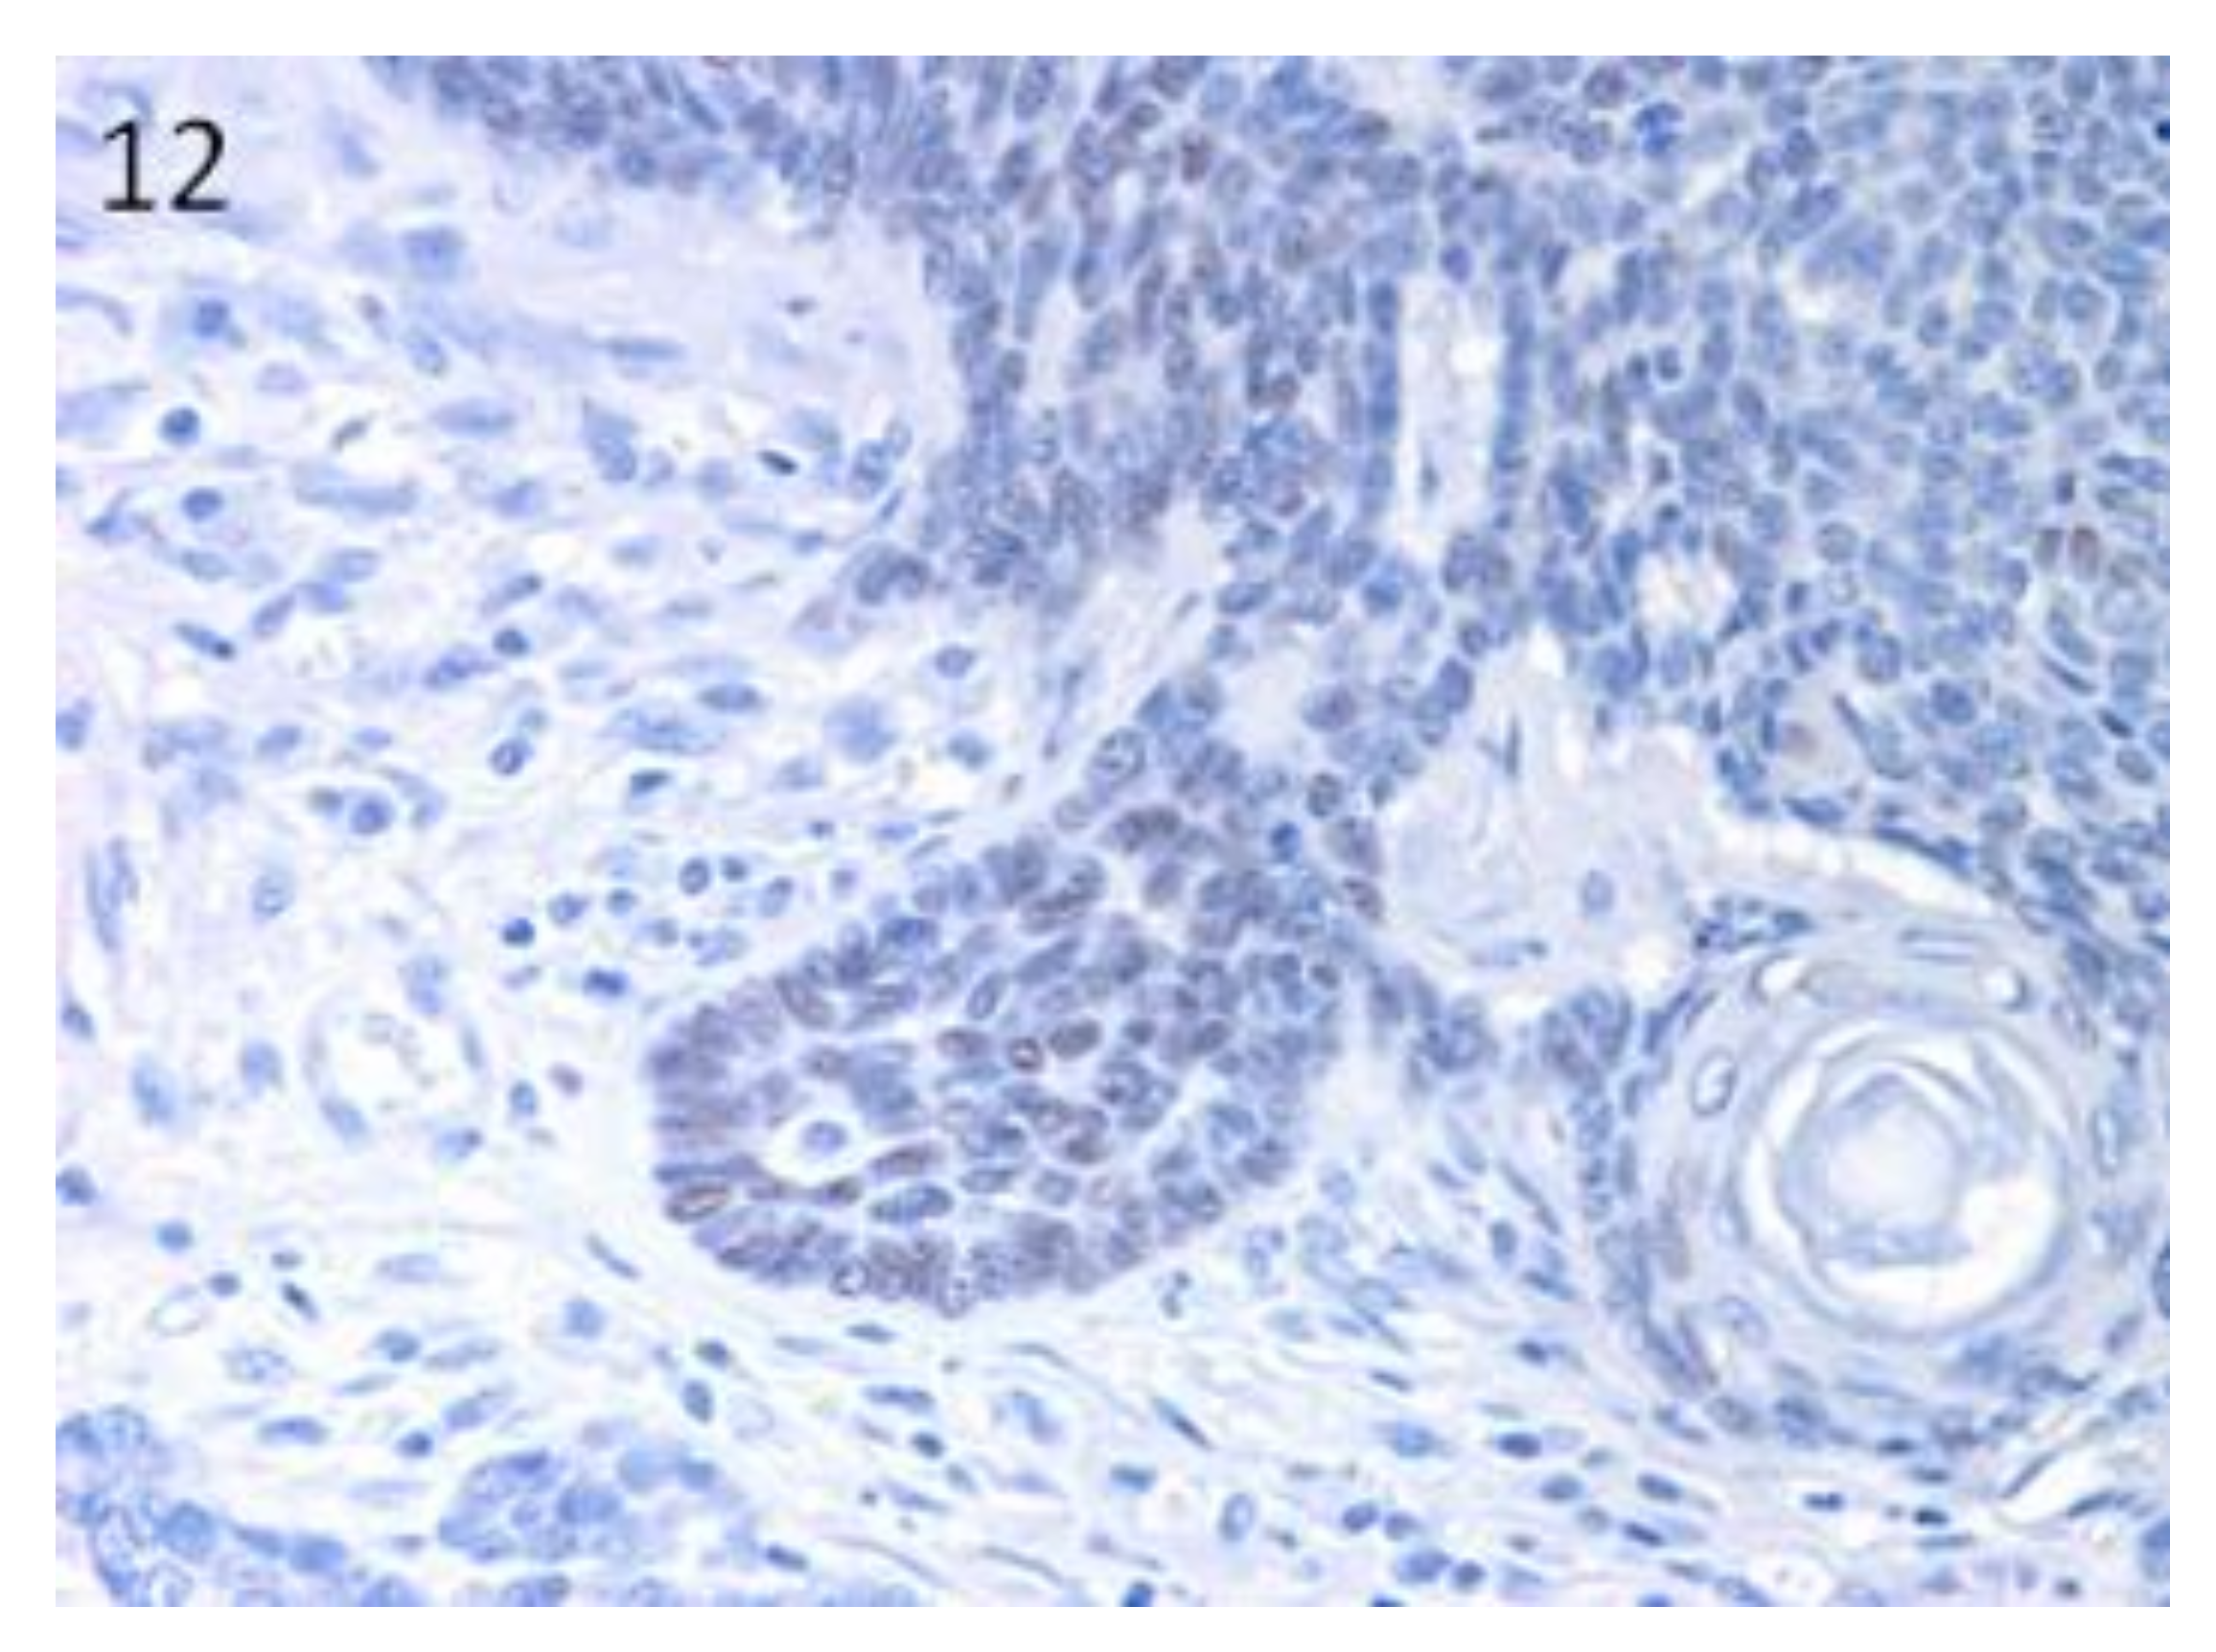

3.2. Stem Cell Marker Analyses in Epidermal Tumours. Lgr5 and Sox9 are Downregulated Compared with Normal Skin

3.3. Stem Cell Marker Analyses in Hair Follicle Tumours. TB Samples Show the Highest mRNA Expression of Lgr6, Lgr5 and Sox9, that are Potentially Useful Markers in Differential Diagnosis with BCC